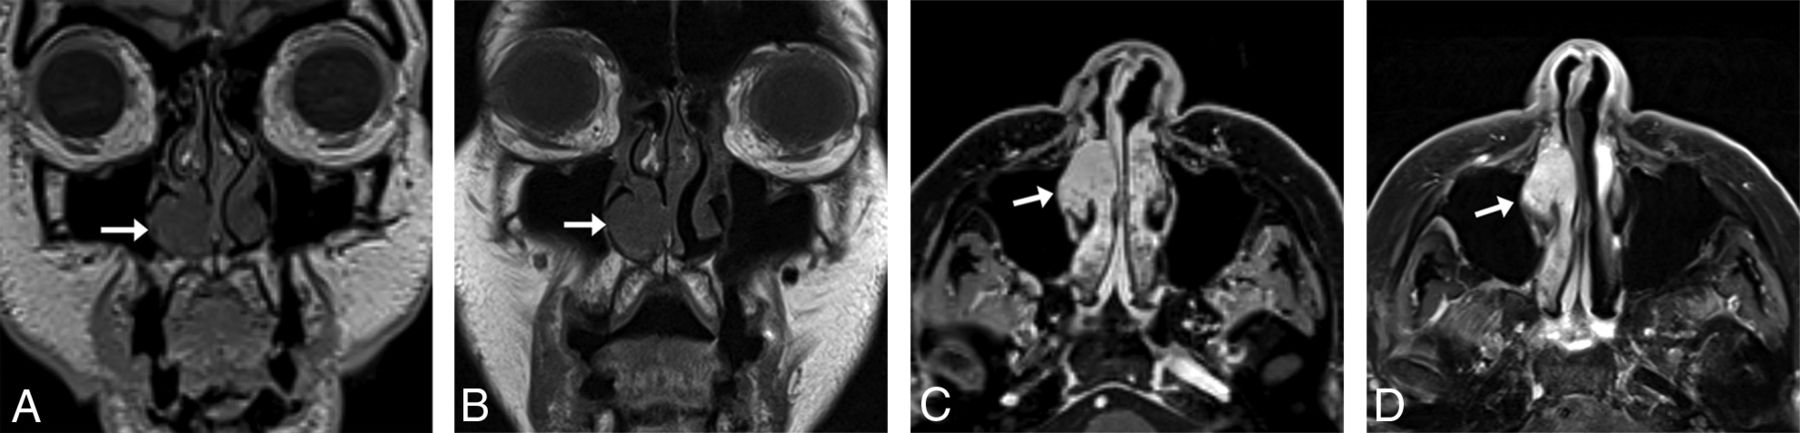

For sinus imaging, we acquired data in the coronal plane, from the tip of the nose to the vertebral bodies, to minimize the scan range and scan times. We show sample images of this protocol compared with 2D images for an 83-year-old woman with a stable untreated nasal cavity mass of unknown pathology in Fig 5.

An 83-year-old woman with melanoma and a stable untreated nasal cavity mass of unknown pathology with sinus protocol MR imaging. T1 SPACE coronal acquisition (A) performed with 1-mm3 (1.0 mm isotropic) voxels shows a mass (arrow) along the anterior aspect of the right inferior turbinate, seen similarly on the 2D T1-weighted image (B) with 0.8-mm3 (3 × 0.5 × 0.52 mm) voxels. The T1 VIBE Dixon axial reformat (C) shows the mass (arrow) to advantage compared with the 2D T1-weighted image (D) with spectral fat suppression; the former shows the extent of the mass relative to the more heterogeneously enhancing turbinate. The 3D images were acquired on a 3T Magnetom Vida system 6 months following the acquisition of the 2D images on a 3T Magnetom Skyra system (Siemens).